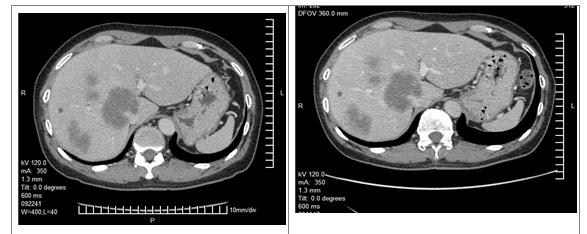

更改化疗方案: FOLFIRI+ bevacizumab 4次

评估:PR

3、关于转化治疗患者的评估:治疗2个周期评估属于SD还是PD?如果是SD,会不会再治疗2个周期患者会出现PR?

一般化疗最佳疗效出现在3-4个月,过早评估是否能反映真实的情况?该患者治疗2个周期后影像学评估提示肿瘤大小只有略微的改变,是否符合PD?如果是SD,会不会再治疗2个周期患者会出现PR?后续的FOLFIRI+Bev会不会是治疗时间累积足够了才体现出PR?各大指南推荐转化治疗首次评估为治疗后2个月(CSCO指南推荐每6-8周),若首次评估无疗效则建议更换方案。

2程化疗后展示的患者肝脏CT无明显改变,评价为PD的原因不明。若患者因肝脏或其他部位出现新发病灶出现了病情进展,可考虑二线采用FOLFIRI联合贝伐单抗,4程化疗后肝脏病灶明显减少、缩小,评价为PR。因贝伐单抗使用后需暂停6周以上才能进行手术,因治疗间隔太长,建议该患者在停用贝伐单抗期间进行FOLFIRI方案化疗2至3疗程。手术切除原发灶和肝转移灶,病理已确认。其后患者进行了术后辅助化疗4程,患者术前行化疗4程,仅出现Ⅱ度骨髓抑制,根据NCCN指南术后可建议其行8程FOLFIRI方案或2-3程FOLFIRI方案加6-5程FOLFIRI联合贝伐单抗方案化疗,达到共6个月的围手术期化疗。

此病例患者首先因为发现肝占位入院,完善检查,诊断升结肠癌 肝转移,原发证升结肠肿瘤可手术切除,但肝内病灶多发(6个),尤其侵犯门静脉主干分叉处,该病例不能归于寡转移疾病。经过MDT会诊,转移灶初治时不可切除,暂无R0手术切除可能,鉴于原发升结肠病灶没有梗阻、出血等症状,一致建议选择转化化疗,降期争取手术治疗是其目的。依据ESMO分组意见,该病例属于组1患者。尽管是一线转化化疗效果欠佳,但是bevacizumab联合FOLFIRI的化疗获得了明显的PR效果,转化为可切除。这个病例显示出如果治疗目标是从不可切除转化为可切除,bevacizumab联合化疗还是有较好的肿瘤退缩效果。该患者总体生存达2年以上,整体治疗是成功的,MDT讨论决策至关重要。但术前评估、手术时机的选择、以及靶向用药等也存在一些需要进一步讨论的问题。